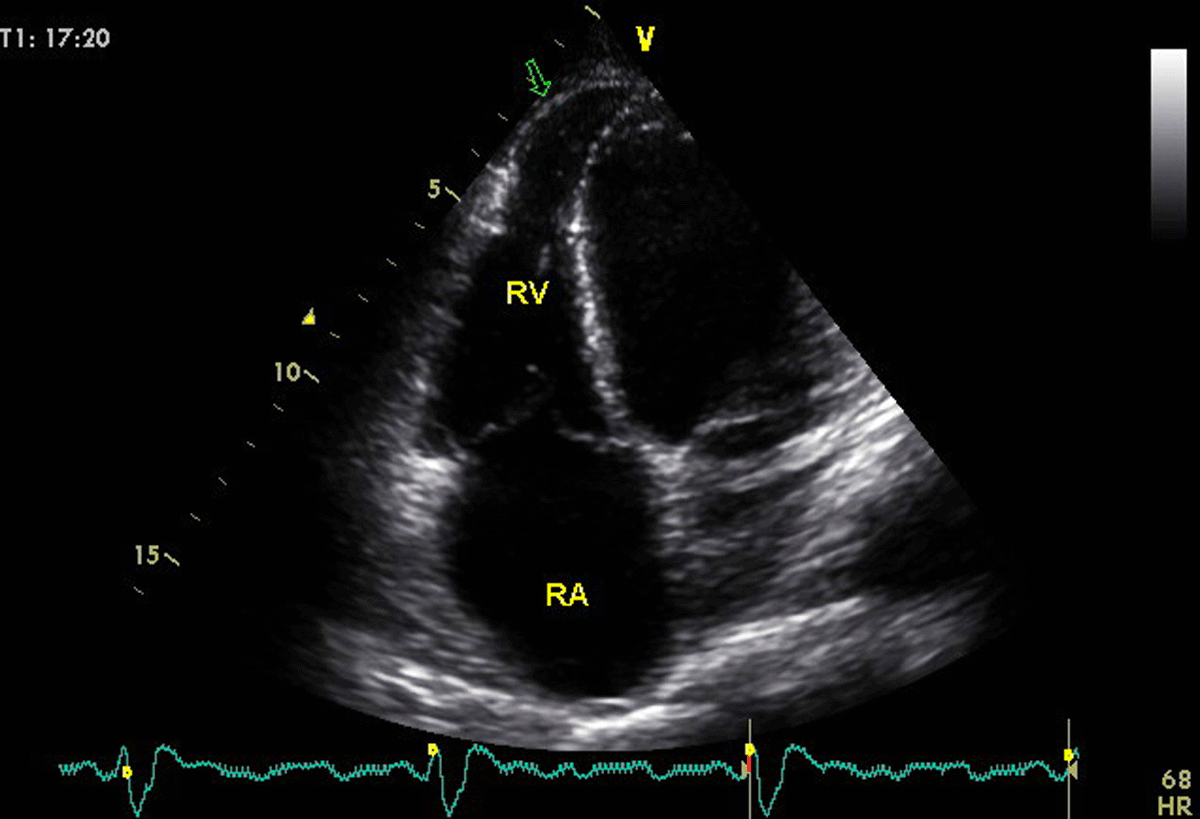

Right ventricular aneurysms are uncommon, but some patients have apical aneurysms affecting both ventricles (Figure 4). It is important to check for the presence of thrombi in the RA and RV.

Figure 4

A young patient with Chagas disease presenting with biventricular dysfunction. Arrow in the 4 chamber-view, optimized to visualize the right ventricle, shows the infrequent finding of right ventricular aneurysm. Image: Marcia Barbosa. Reproduced with permission of the photographer.

Right ventricular systolic involvement is a marker of ChD severity and represents a strong predictor of mortality [5658]. Furthermore, it has also been reported to be an important determinant of exercise capacity in ChD. Right ventricular systolic annular velocity by tissue Doppler imaging was associated with peak VO2, regardless of the influence of age, gender, and LV systolic function [59]. Table 5 summarizes recommendations regarding RV echo measurements.